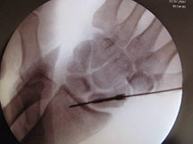

El paciente de edad se beneficia habitualmente del tratamiento conservador con escayola. En el paciente joven el desplazamiento suele ser difícilmente manejable con inmovilización con yeso por lo que es frecuente la realización de una pequeñaintervención para la recuperación anatómica de la muñeca pudiendo reincorporarse a su actividad habitual en el menor tiempo posible y con el menor riesgo de complicaciones.Dentro de la región anatómica de la muñeca se encuentran los huesos del carpo. El hueso escafoides es el que se fractura con más frecuencia tras caídas sobrela mano en extensión. Es por ello una lesión característica en deportes como motociclismo, ciclismo y patín donde se pueden sufrir traumatismos a gran velocidad. El dolor se localiza siguiendo el eje del pulgar pero a nivel de la muñeca y el dolor a la palpación en esta zona (tabaquera anatómica) es extremo. Las fracturas desplazadas se suelen estabilizar quirúrgicamente sin cicatriz,a través de la introducción percutánea de un tornillo intraóseo que permite el inicio de la movilización de la articulación inmediatamente.